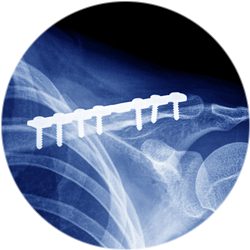

Специалист осуществляет фиксацию отломков титановыми пластинами, спицами, винтами. Если необходимо, то дополнительно ушиваются сосуды и нервы, удаляются пораженные ткани.

Результат операции на ключицу и возможные осложнения

Хирургическое вмешательство, выполненное в полном объеме, имеет высокий результат. Благодаря операции, костные отломки правильно соединяются и прочно фиксируются специальными приспособлениями (винты, гвозди, пластины). Это обеспечивает более быстрое восстановление движений верхней конечности, снижение риска повторного смещения костных фрагментов, полное возвращение к привычной жизни.